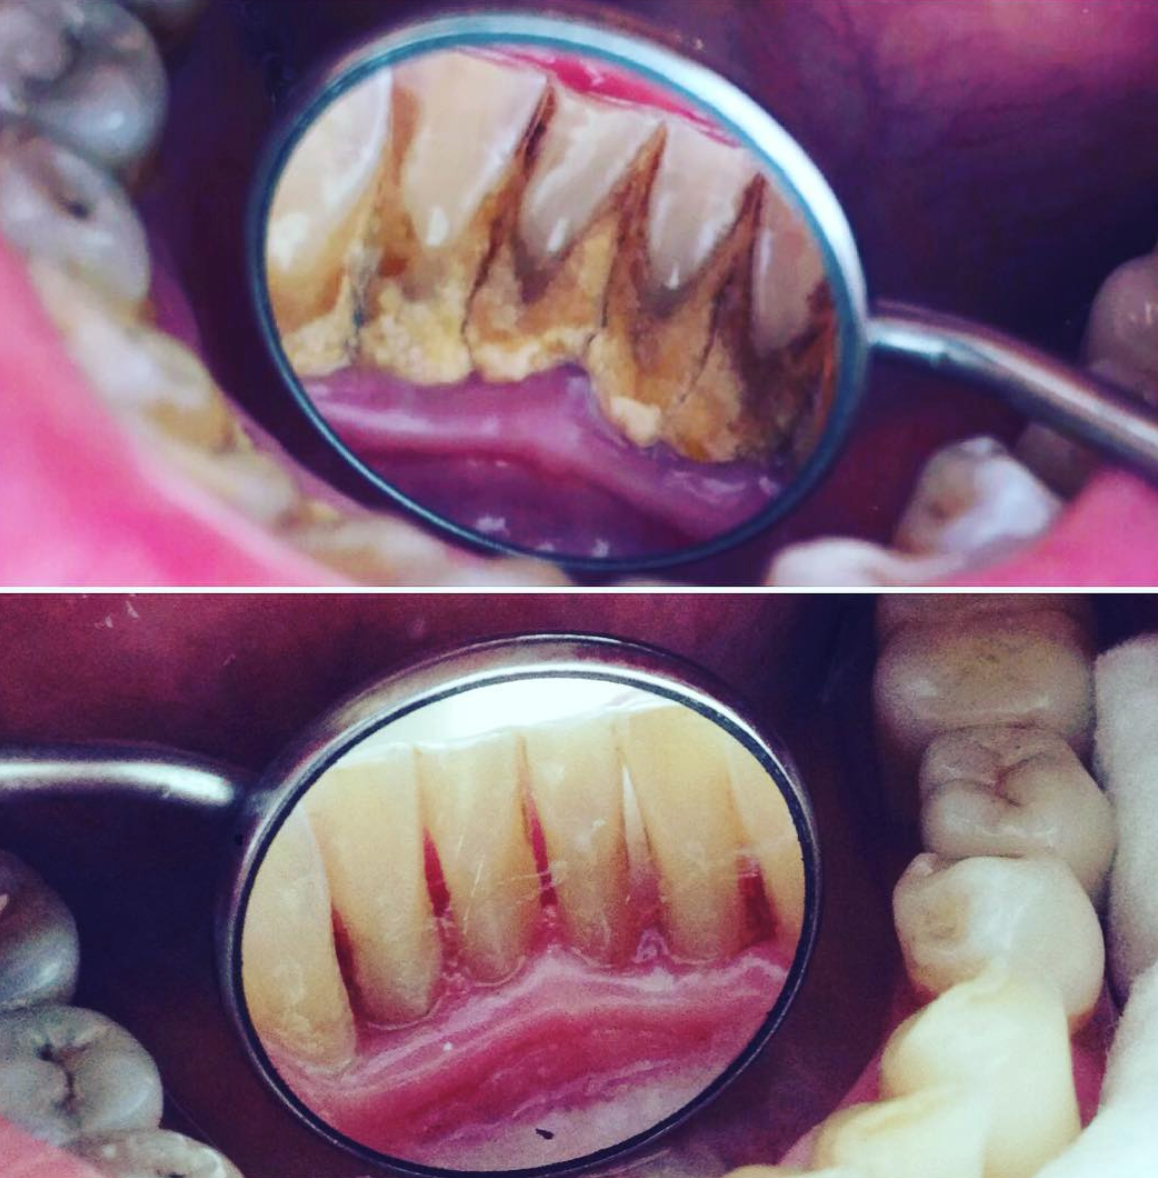

Убрать с эмали налёт и зубной камень

Снятие зубных отложений с помощью ультразвука

Твердые отложения (зубной камень) образуются в межзубных промежутках, на зубах в придесневой и поддесневой областях. Зубной камень может привести к развитию таких заболеваний, как гингивит, пародонтит или кариес. Процедуру проводят ультразвуковым скейлером, который с помощью вибраций удаляет твердые отложения с поверхности зуба.

Чистку делают с помощью ультразвукового скалера, который посылает вибрации на поверхность зуба. Такая технология безопасна и безболезненна. Это отличная альтернатива химическим или механическим способам снятия зубных отложений.